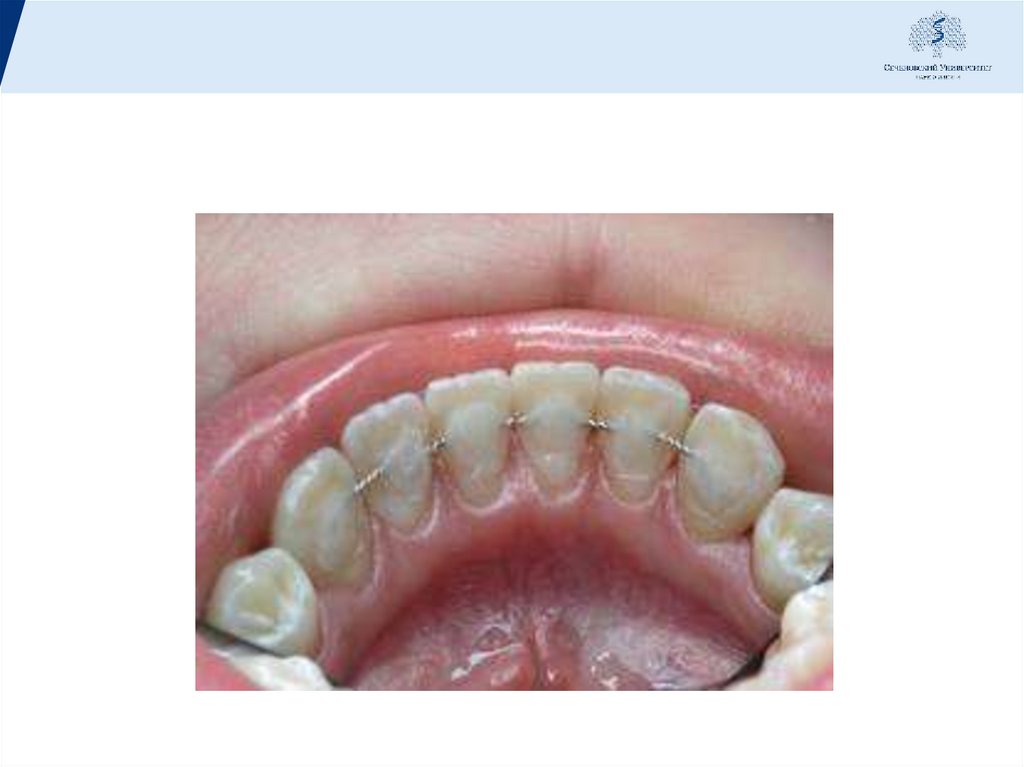

52. Съемные шины

Шинирующие свойства съемных шин обеспечиваются различной комбинацией

непрерывных опорно-удерживающих и перекидных кламмеров, а также разной

формы окклюзионных накладок. Распространению их способствовала разработка

методик параллелометрии, точного литья на огнеупорных моделях, применение

хромокобальтовых сплавов и сплавов из благородных металлов.

Съемные шины могут применяться для шинирования одной какой-либо группы

зубов или всего зубного ряда. При иммобилизации передних зубов шину

желательно доводить до премоляров, а при шинировании боковых - до клыков.

Съемные шины могут включаться в конструкцию дугового протеза как его

составляющая часть. Это шины-протезы:

• шина типа непрерывного кламмера;

• шина-каппа;

• единая шина для всего зубного ряда.

Преимущеста: легко поддаются очистке, меньше

нарушают гигиену полости рта. Нарушения эстетики

минимальны.

можно применять их для профилактики функциональной

перегрузки пародонта, при дефектах зубных рядов с

признаками заболевания пародонта, но без

патологической подвижности зубов.

Изготовление съемных шин производится в лаборатории,

в полости рта больного манипуляции сокращаются. Это

также относится к достоинствам этого вида шинирования.

К недостаткам таких шин относится то, что при

изготовлении их требуется большая точность:

обязательное применение параллелометрии и точного

литья на огнеупорных моделях. При нарушении точности

наложения и снятия шины возможна перегрузка

пародонта отдельных зубов.